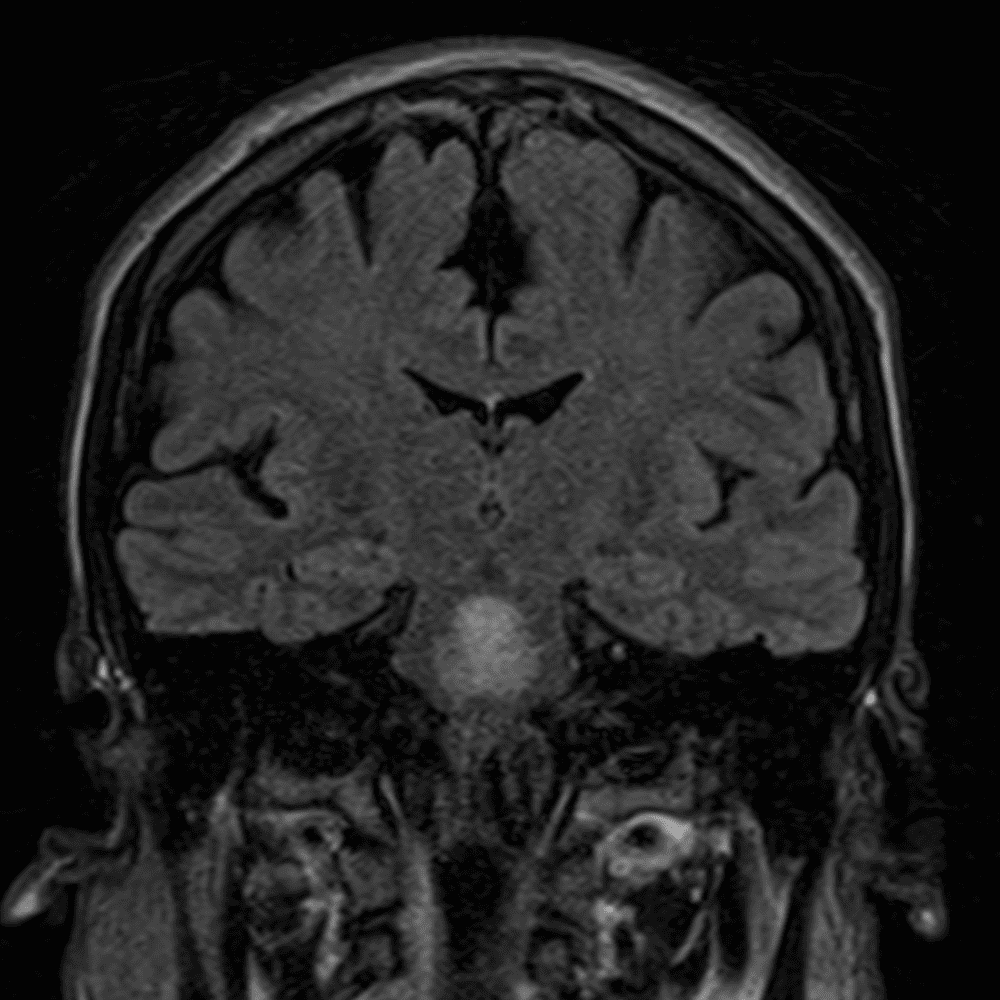

๋‹น์ง ์‹œ ํ”ํžˆ ๋ณผ ์ˆ˜ ์žˆ๋Š” ์‚ฌ๋ก€์˜ ์ „ํ˜•์ ์ธ ์˜ˆ๋ฅผ ํฌํ•จํ•ฉ๋‹ˆ๋‹ค.

39 ์‚ฌ๋ก€

์—ฐ์Šต

๋ฏธ๋ฌ˜ํ•˜๊ฑฐ๋‚˜ ์–ด๋ ค์šด ์‚ฌ๋ก€์™€ ์ผ๋ถ€ ์ •์ƒ ์‚ฌ๋ก€๋ฅผ ํฌํ•จํ•˜์—ฌ ๋‹น์ง์„ ์‹œ๋ฎฌ๋ ˆ์ด์…˜ํ•ฉ๋‹ˆ๋‹ค.

50 ์‚ฌ๋ก€